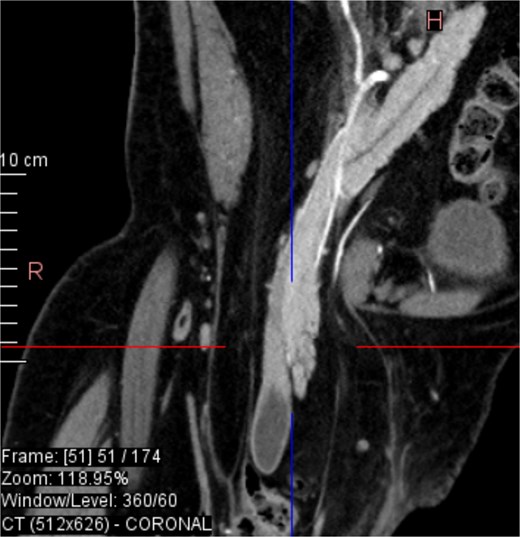

CT imaging (Figs 2–5) revealed a right inguinal hernia containing small bowel loops, ascending colon, the second and third portions of the duodenum, and the pancreatic head. The pancreatic head appeared rotated and displaced inferiorly into the hernia sac, without signs of acute pancreatitis.

Sagittal CT view inguinal hernial sac with pancreatic head and D2 and D3 segment of duodenum.